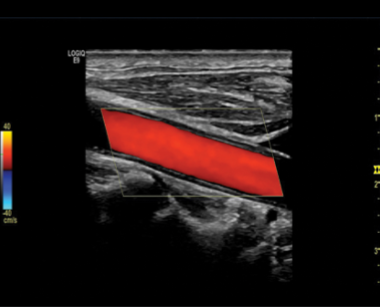

Is this image showing flow towards or away from the transducer?

Towards